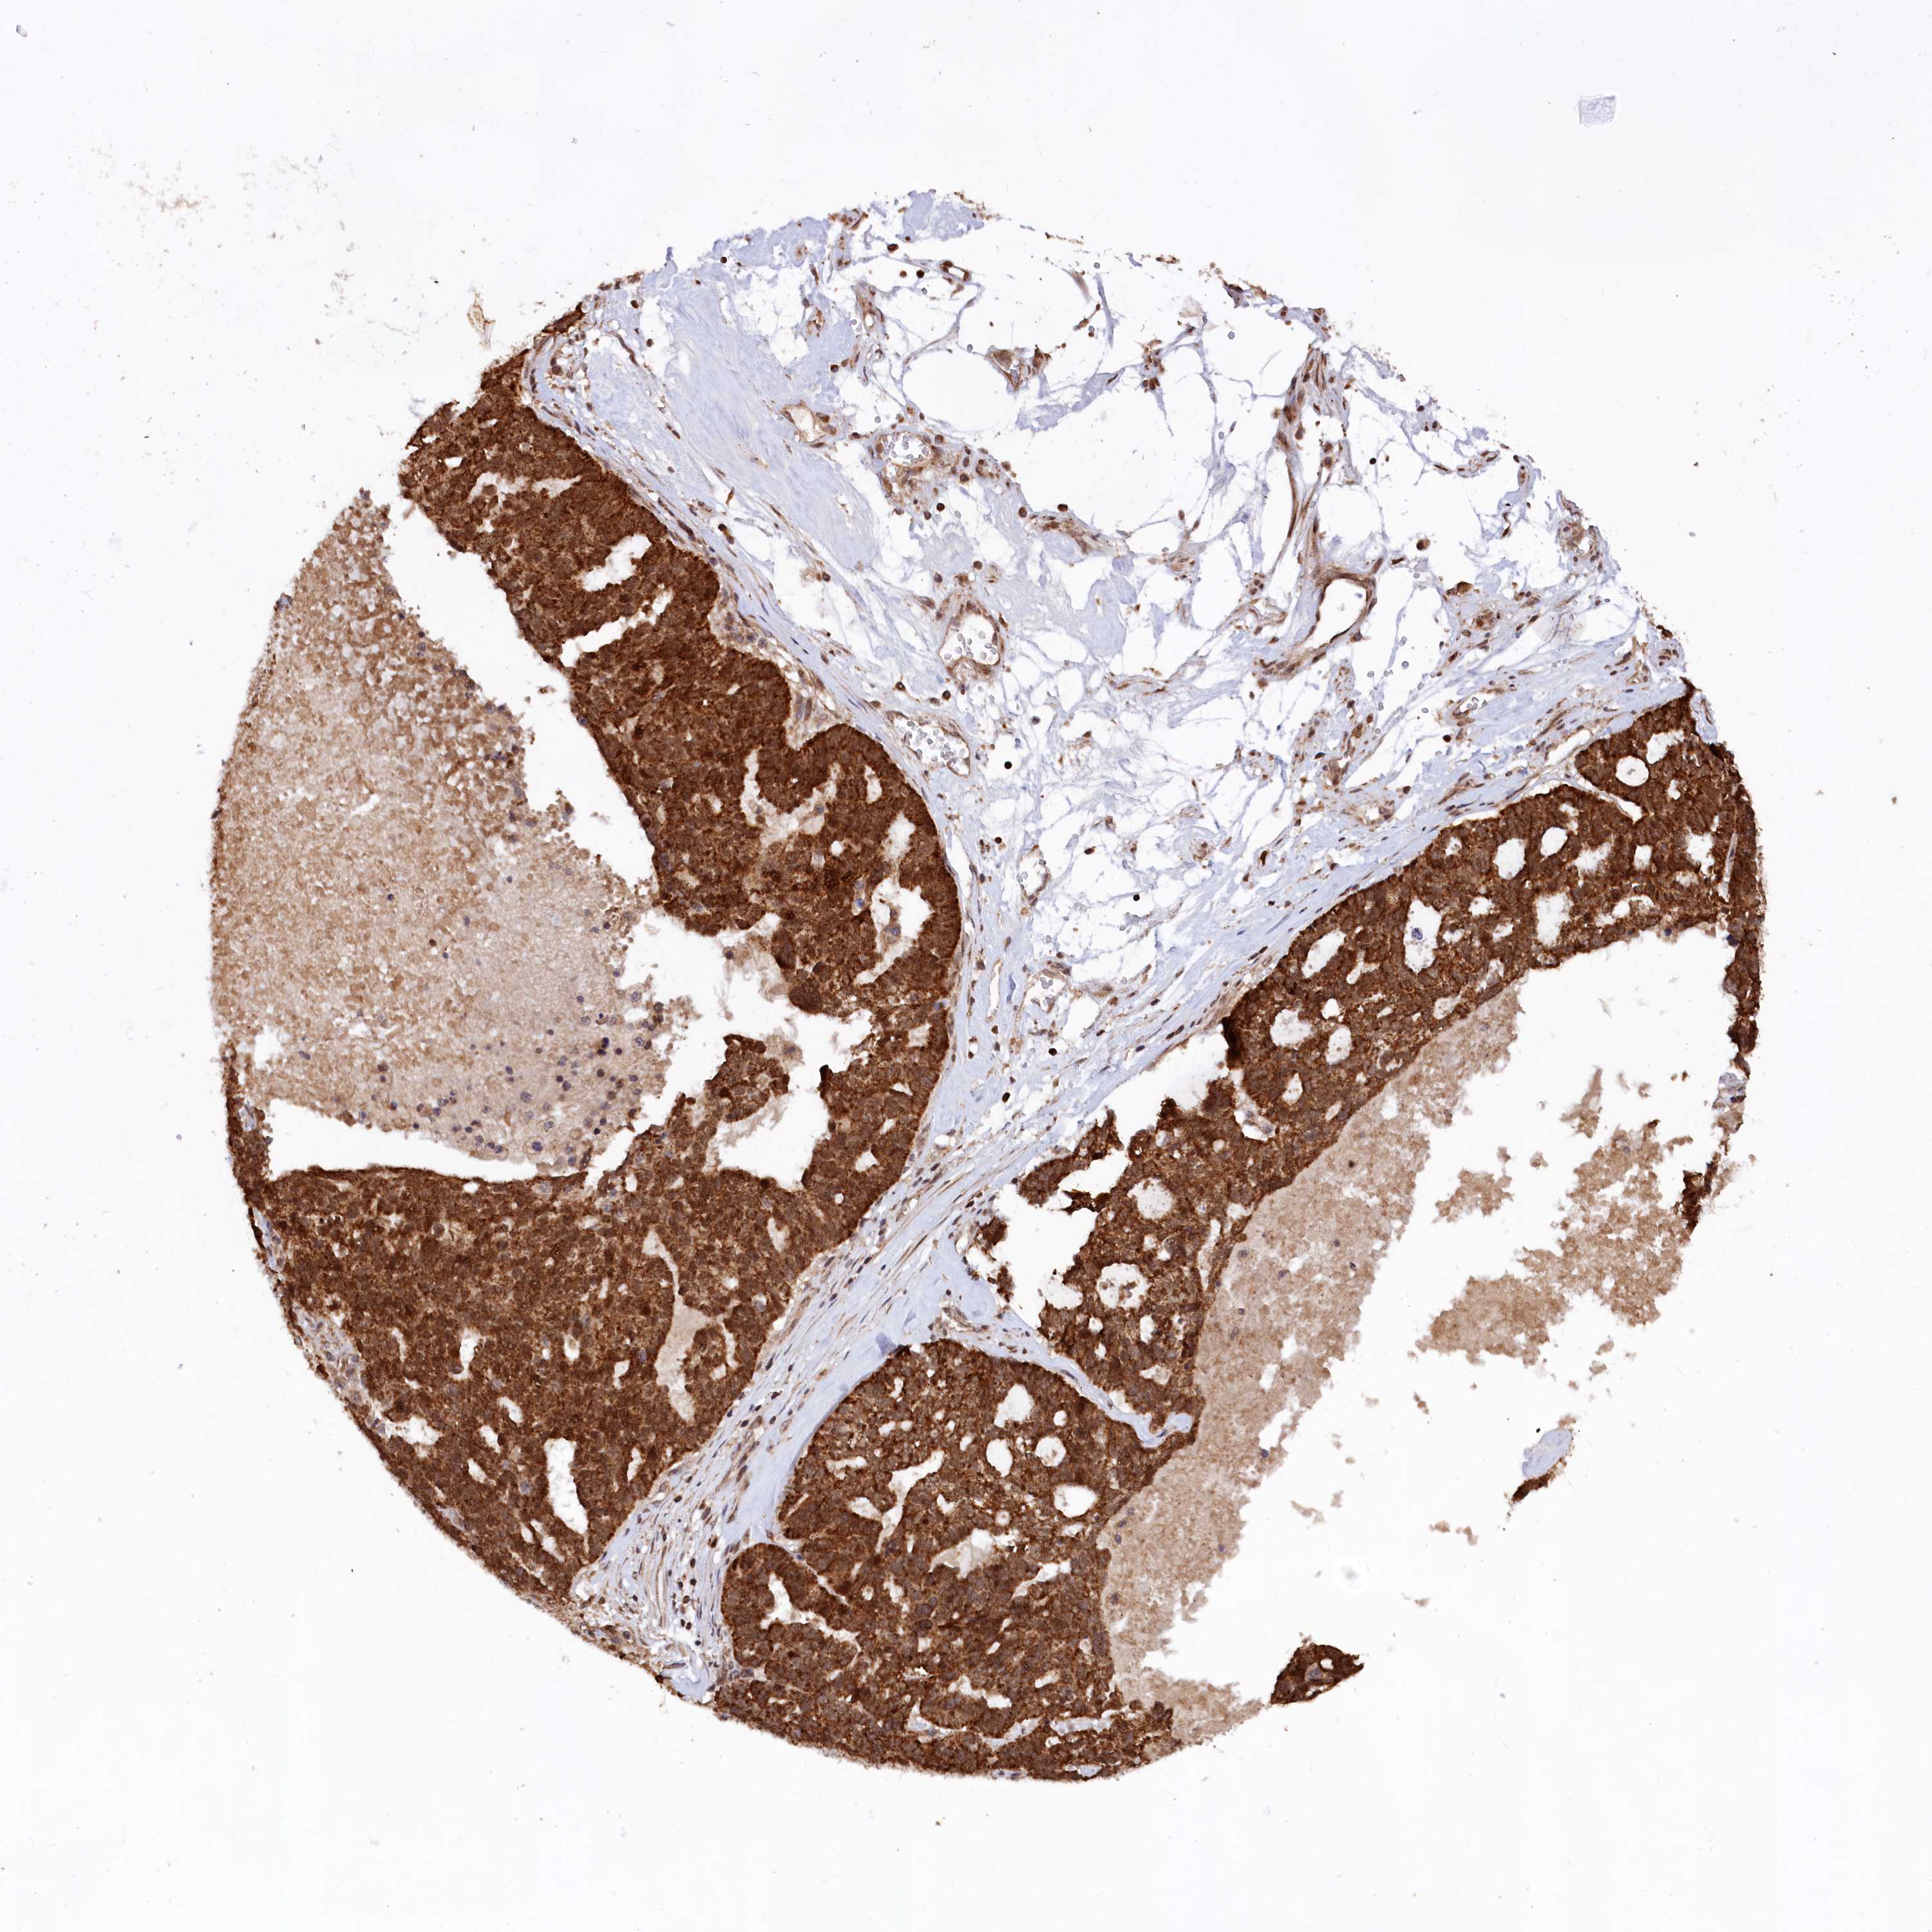

OVARIAN CANCER - Protein expressioni

A mouse-over function shows sample information and annotation data. Click on an image to view it in a full screen mode. Samples can be filtered based on level of antibody staining by selecting one or several of the following categories: high, medium, low and not detected. The assay and annotation is described here.

Note that samples used for immunohistochemistry by the Human Protein Atlas do not correspond to samples in the TCGA dataset.

Antibody stainingi

Antibody staining in the annotated cell types in the current human tissue is reported as not detected, low, medium, or high, based on conventional immunohistochemistry profiling in selected tissues. This score is based on the combination of the staining intensity and fraction of stained cells.

Each image is clickable and will lead to virtual microscopy that enables deeper exploration of all samples and also displays staining intensity scores, fraction scores and subcellular localization as well as patient and tissue information for each sample.

Antibody HPA039162

Cystadenocarcinoma, serous, NOS

Carcinoma, endometroid

Cystadenocarcinoma, mucinous, NOS

Carcinoma, NOS